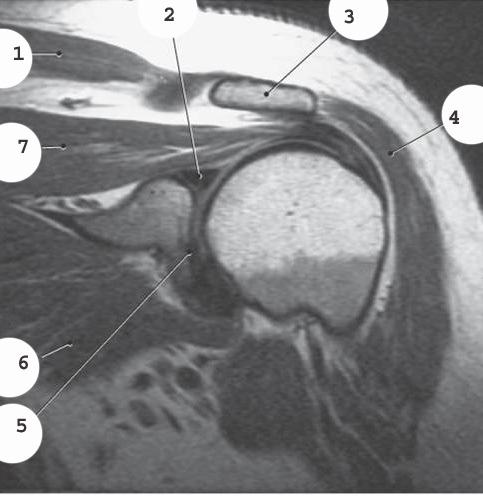

1

Aorta

2

Left common iliac artery

3

Left internal iliac artery

4

left external iliac artery

5

left femoral artery

popliteal artery

quadricep tendon

lateral colateral ligament